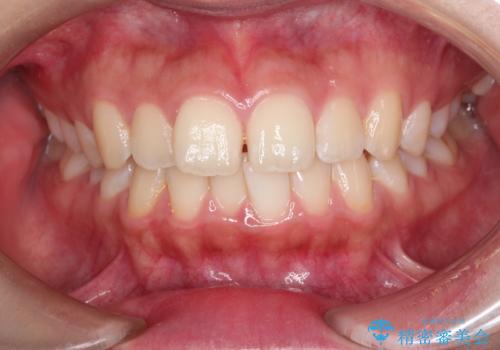

【インビザライン】前歯のねじれを治したい。

- 前歯の凸凹を主訴に来院されました。

スペースを作るために顎間ゴムを使用して、奥歯の遠心移動をおこない配列しました。

奥歯の遠心移動を行うことで、犬歯関係も良い状態に仕上げることができました。